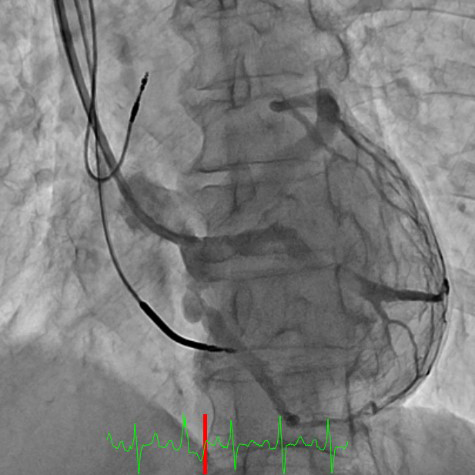

両心室ペーシング機能付き植込型除細動器移植術

(血管撮影)